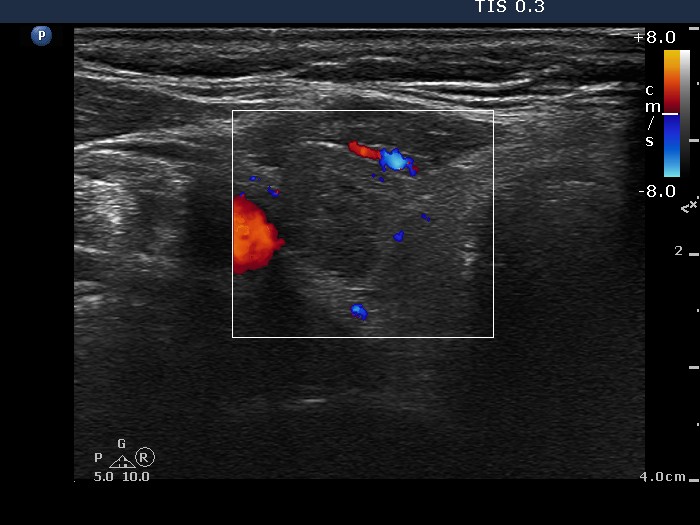

100 consecutive cases of papillary cancer - case 026 (ultrasonographic picture 5)

Right lobe, transverse scan, color Doppler mode. This lesion is avascular.